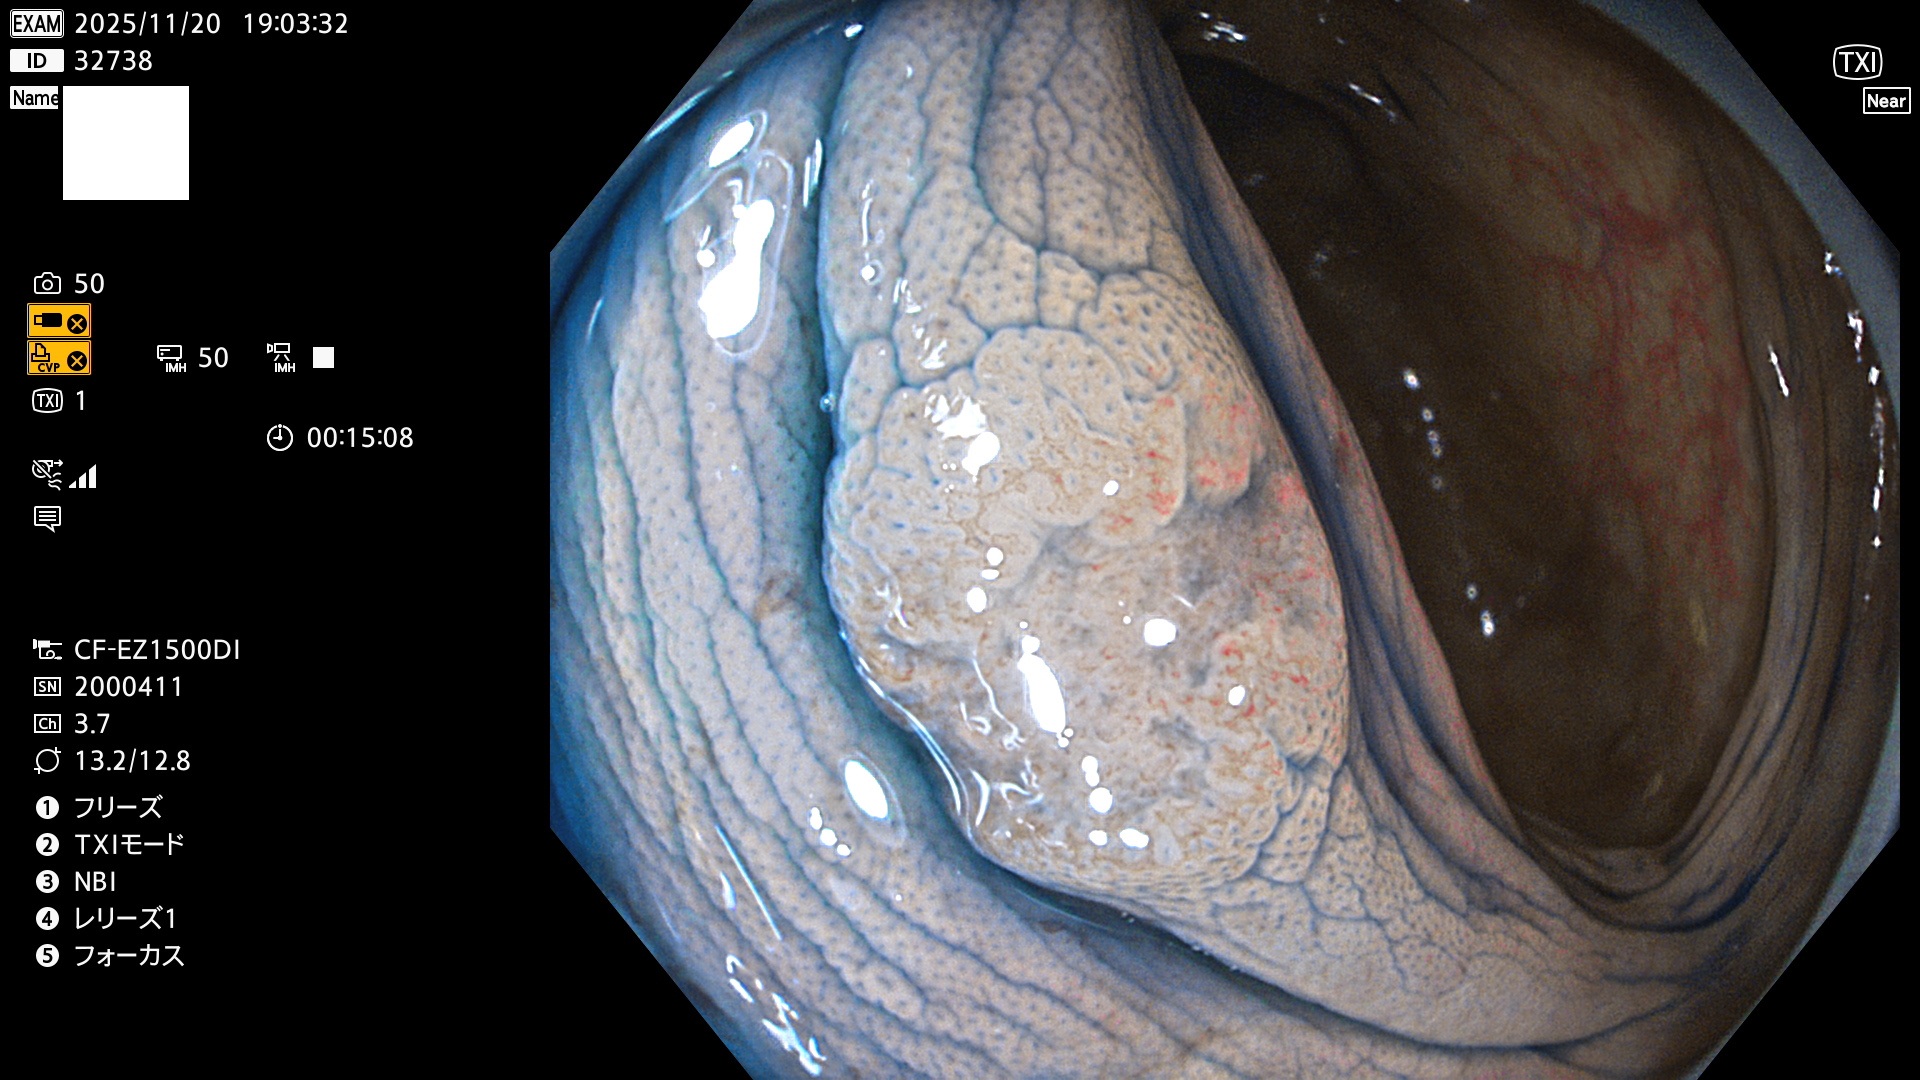

完全に平坦な物をUb、陥凹している物をUcと呼びます。Ubは認識が困難で、Ucはびらん(炎症)と紛らわしいために見落とされやすく、「内視鏡後・大腸癌」の原因になります。

専門的)Uc=De Novo癌? 内視鏡の解像度が低かった時代、このような説もありました。しかし今日の高精度内視鏡では良性の微小なUc型腺腫(APC遺伝子異常の腺腫)が日常的に見つかります。Ucこそが多段階発癌(Adenoma-Carcinoma Sequence)のMain Routeです。

毎週の検査(木・金・土・日)に発見されたUbとUc型・腺腫を、その週の日曜の夜にUPし1週間、提示します。

2025年11月20日〜11月23日の4日間(40件)8個 (Uc_ADR=8個/40人=20%)